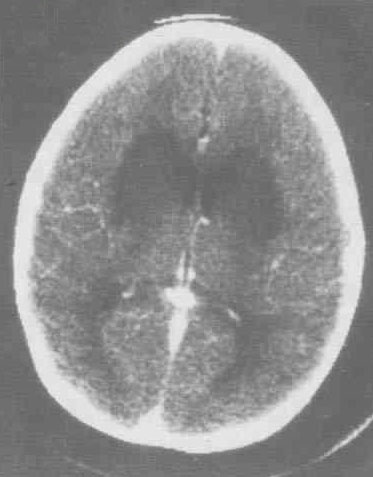

腦炎是指腦實質(zhì)受病原體侵襲導(dǎo)致的炎癥性病變。患者主要表現(xiàn)為發(fā)熱、頭痛、惡心、嘔吐,也可以出現(xiàn)偏側(cè)肢體感覺障礙、運動障礙、言語功能障礙,也可以出現(xiàn)頭暈和平衡障礙。也可能會出現(xiàn)精神癥狀和癲癇發(fā)作,嚴(yán)重時可能會出現(xiàn)意識障礙,包括嗜睡、昏睡和昏迷。那么腦炎是怎么引起的呢?

引起腦炎的原因很多,各種致病物質(zhì)都可引起腦炎,主要由細(xì)菌、病毒、螺旋體、立克次氏體、寄生蟲等病原微生物或自身免疫性疾病等引起。一般是由于這些致病物質(zhì)突破了人體的血腦屏障而導(dǎo)致的。在腦炎之前,患者可能有呼吸道感染病史或者腸道感染病史,由于體質(zhì)較弱或者致病物質(zhì)太多,而突破血腦屏障,引起腦炎發(fā)生。有一些疾病可能本身就是直接打擊腦部的,比如流行性腦脊髓膜炎,流行性乙型腦炎等,這些病毒或者細(xì)菌直接損害腦細(xì)胞而引起腦損傷。